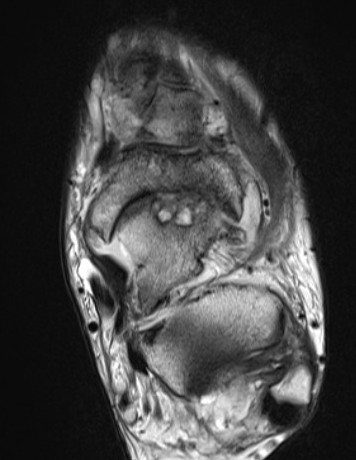

MRI